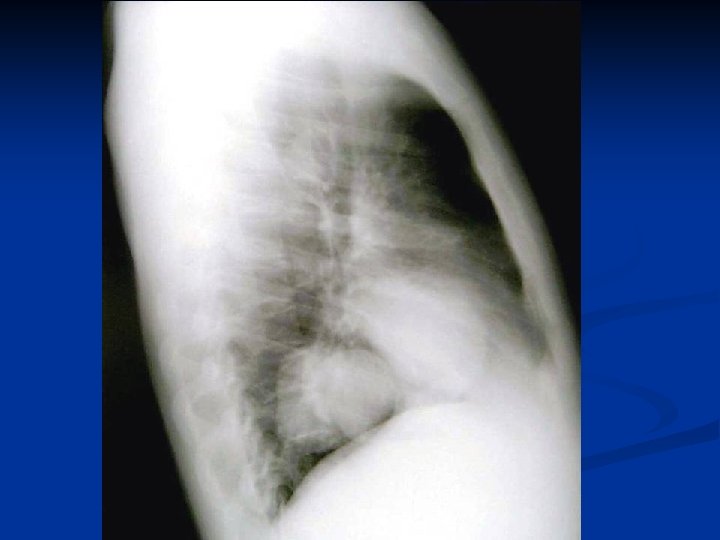

Caracteristici generale n n n Boala parazitara determinata de Taenia echinococcus granulosus. Descrisa inca de pe vremea lui Hipocrat si a lui Galen. Termenul de “chist hidatic” utilizat de Rudolphi in 1908. Localizarea pulmonara este a doua ca frecventa dupa cea hepatica. Boala cu distributie endemica in regiunea mediteraneana, Orientul Mijlociu, Australia, Noua Zeelanda, America de Sud.

Material si Metoda n Studiul de fata analizeaza retrospectiv 162 de cazuri operate in perioada 1999 – 2003.

Metode de diagnosticare